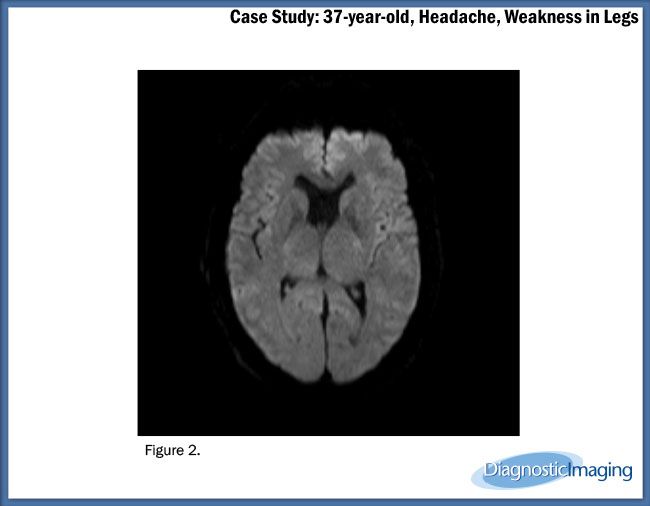

Case History: 37-year-old patient presented with headache and muscle weakness in legs.

Case History: A 37-year-old patient presented with headache and muscle weakness in legs.